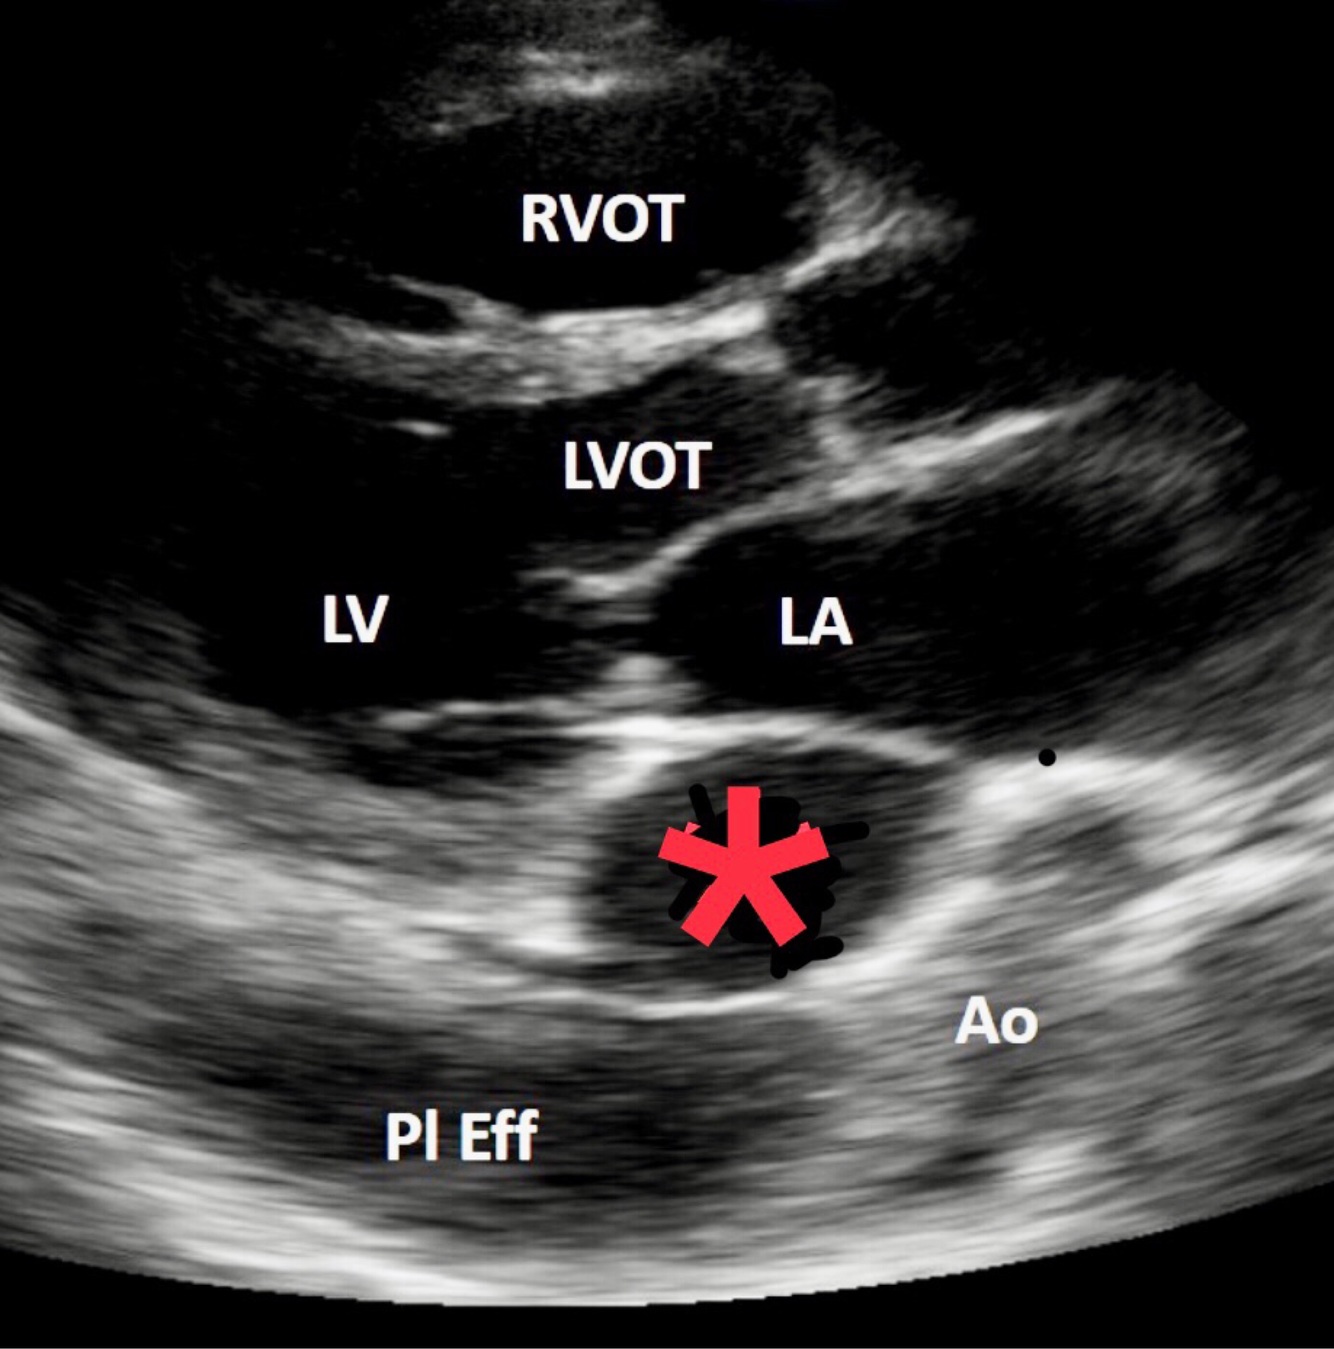

Name this abnormal structure

Dilated coronary sinus